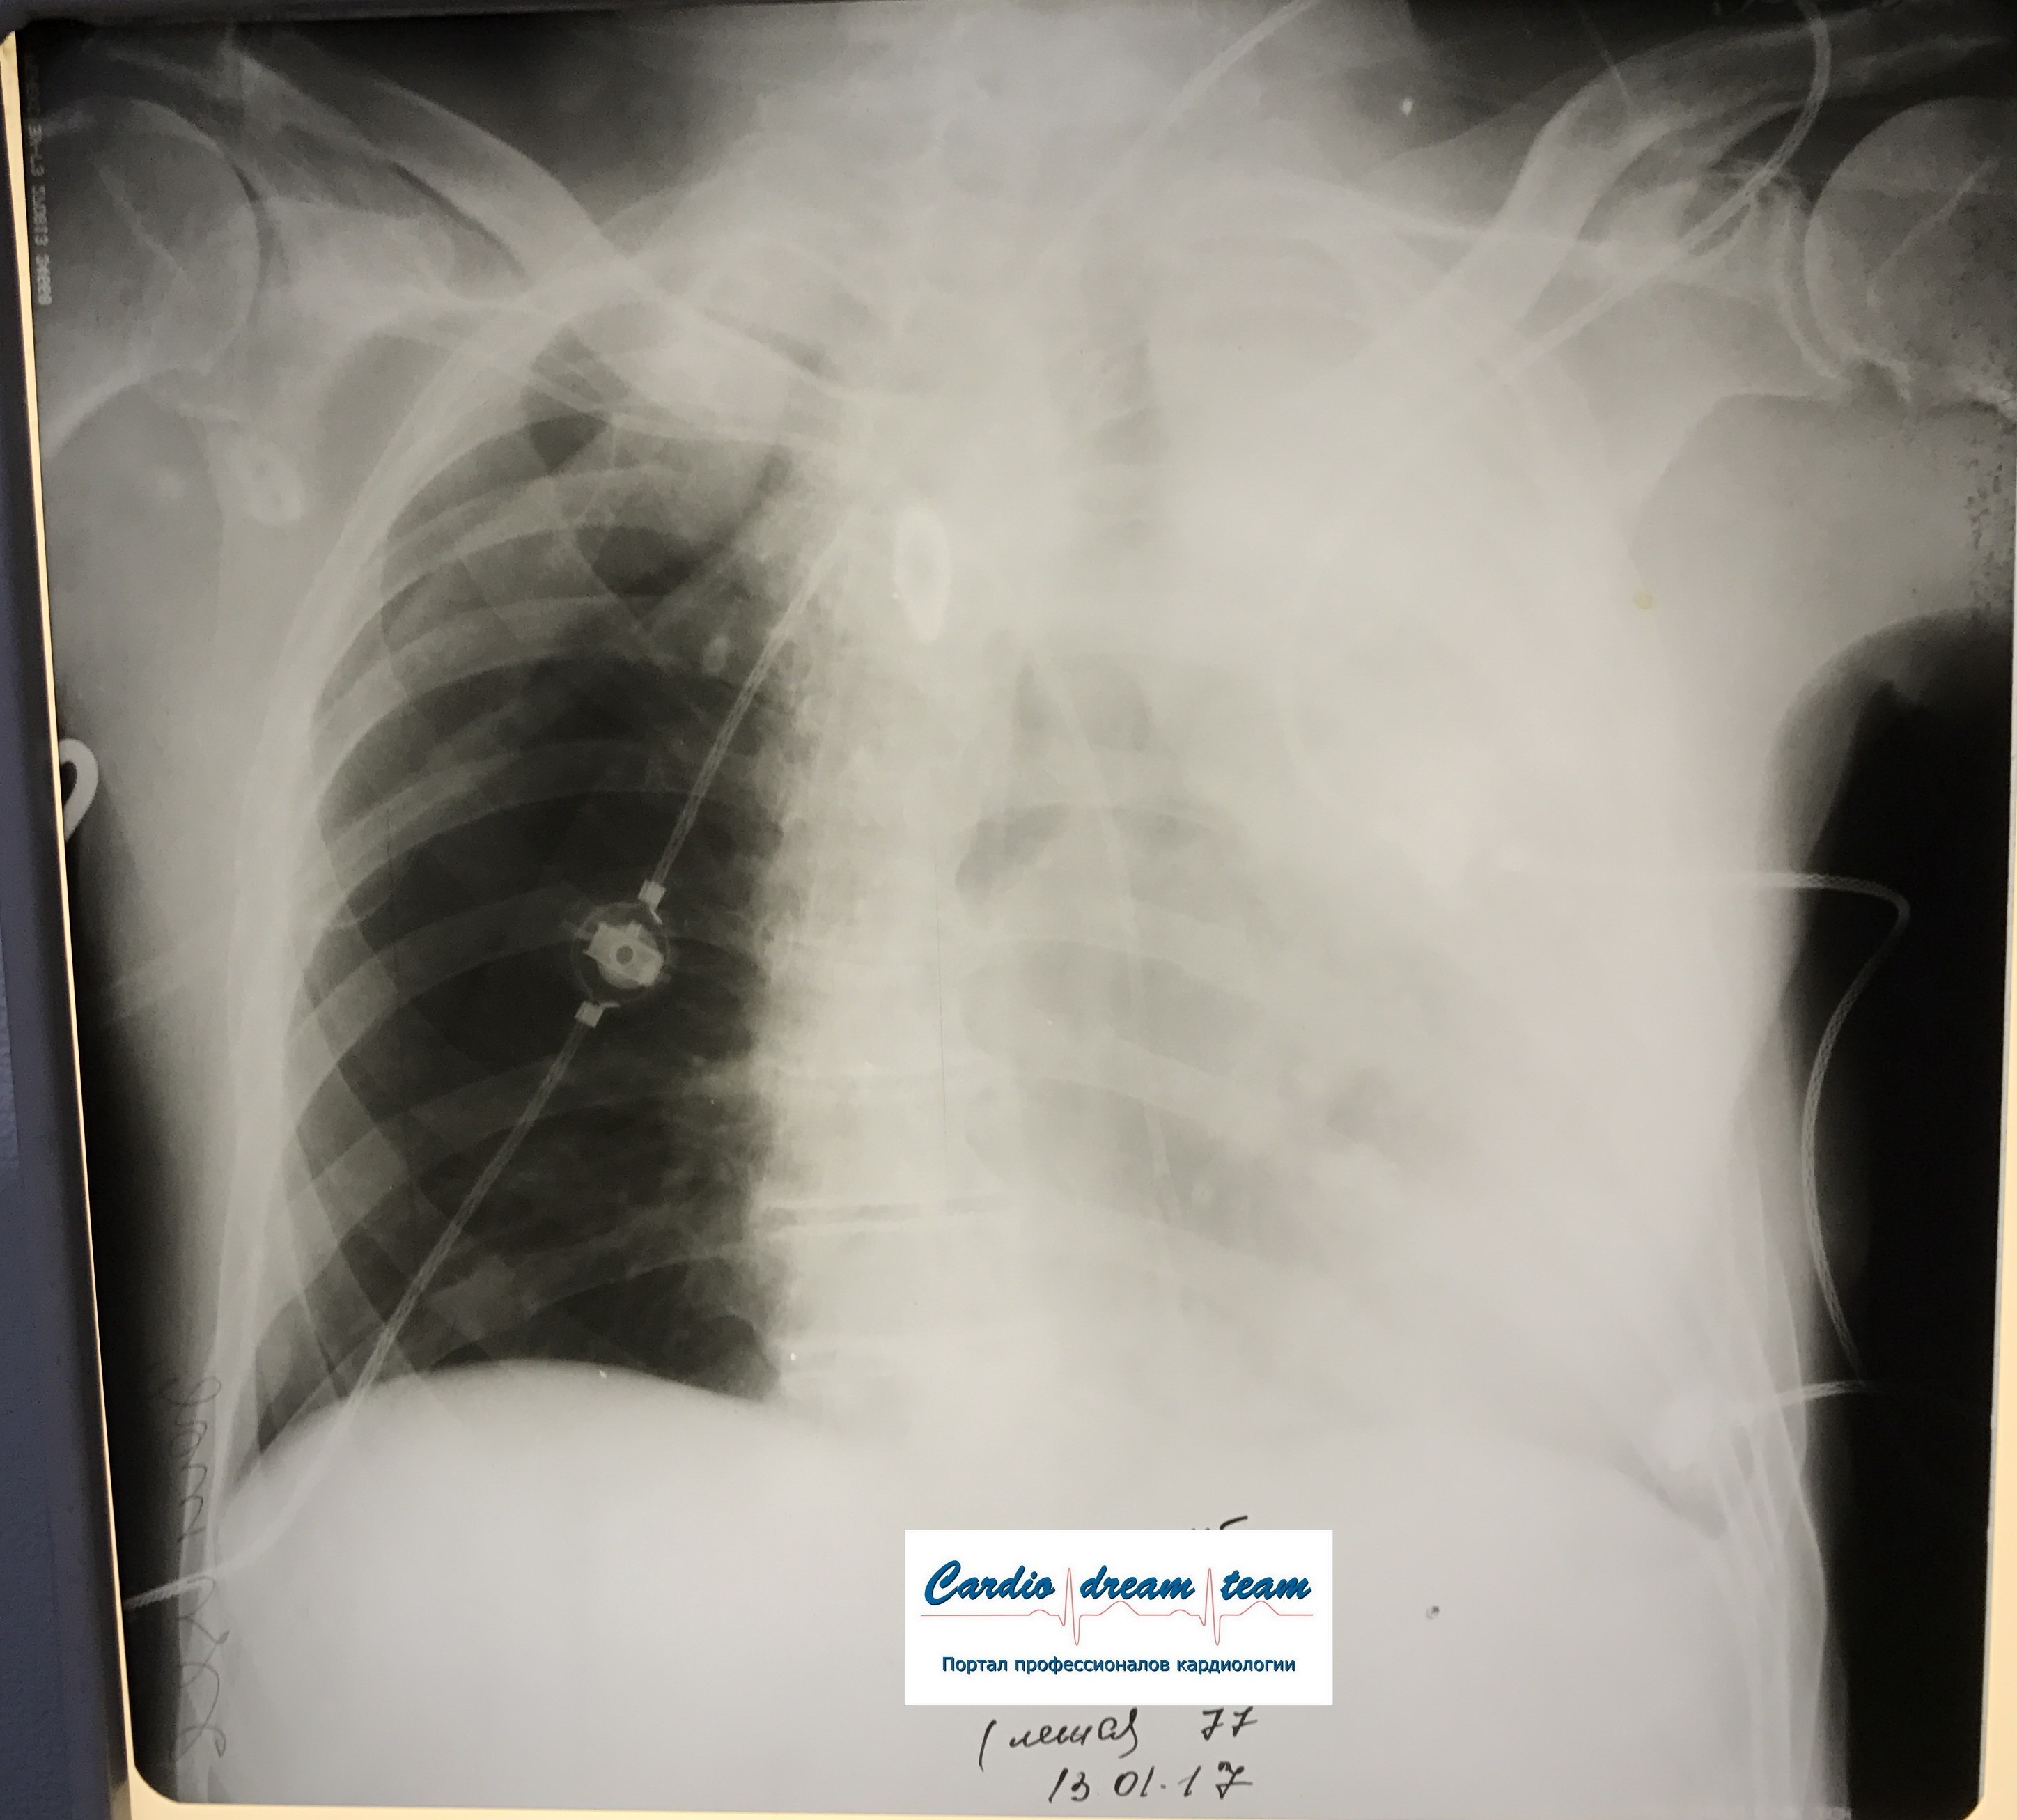

Ателектаз слева. Гнойный эндобронхит с закупоркой бронхов гноем.

IMG_8216.png

IMG_8216.png [ 1.37 MiB | Просмотров: 22487 ]